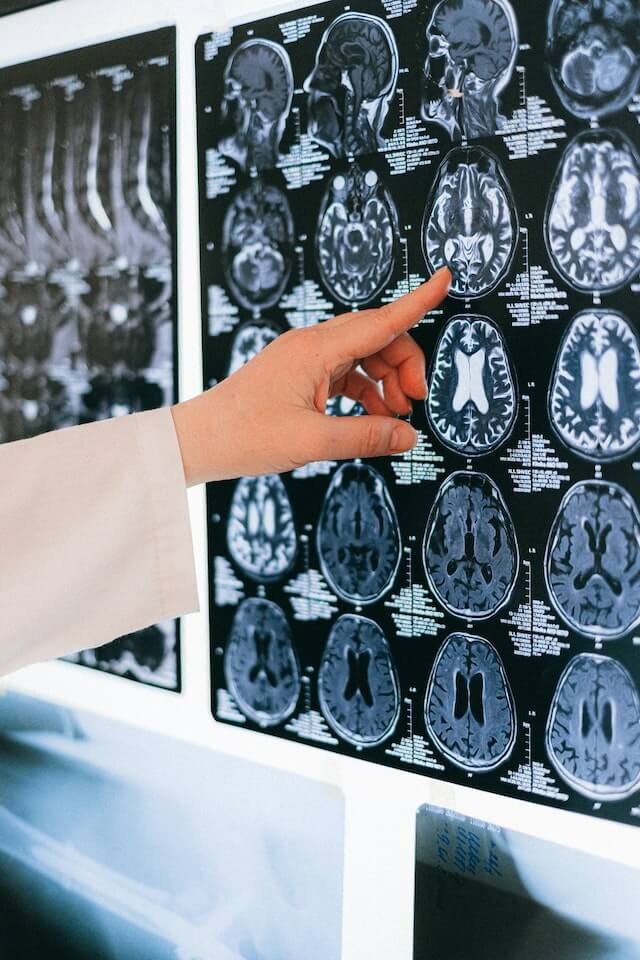

간질 진단의 첫 번째 단계는 병력 및 신체 검사입니다. 이전 발작 및 신경 장애를 포함하여 환자의 증상 및 병력을 검토합니다. 환자가 복용하고 있는 약물과 간질의 가족력에 대해서도 알아야 합니다. 신체 검사 중에 의사는 근력 약화 또는 조정 문제와 같은 신경학적 문제의 징후를 확인합니다. 발작을 일으킬 수 있는 다음과 같은 다른 조건을 확인하는 절차가 필요할 수도 있습니다. B. 발열 또는 감염. 자기공명영상(MRI) 또는 컴퓨터 단층촬영(CT)과 같은 영상 방법은 종종 간질을 진단하는 데 사용됩니다. 이러한 검사는 발작을 일으킬 수 있는 종양이나 반흔 조직과 같은 뇌의 구조적 이상을 식별하는 데 도움이 될 수 있습니다. EEG는 간질을 진단하는 데 사용되는 또 다른 일반적인 도구입니다. EEG 동안 두피에 전극을 배치하여 뇌의 전기적 활동을 기록합니다. 이 테스트는 간질을 나타낼 수 있는 비정상적인 전기 활동 패턴을 식별하는 데 도움이 될 수 있습니다. EEG에는 몇 가지 유형이 있습니다. 첫째, 일상적인 EEG는 사람이 깨어 있는 동안 수행됩니다. 일반적으로 완료하는 데 약 30-60분이 소요됩니다. 다음으로 환자가 일정 기간 동안 잠을 자지 않은 후에 수행되는 수면 박탈 EEG가 있습니다. 이것은 뇌에서 비정상적인 전기 활동을 포착할 가능성을 높이는 데 도움이 될 수 있습니다. 응급 EEG는 보통 24-72시간 동안 휴대용 EEG 기계를 착용한 상태에서 수행됩니다. 병원 환경 밖에서 발생할 수 있는 발작을 식별하는 데 도움이 될 수 있습니다. 어떤 경우에는 간질을 진단하기 위해 비디오 EEG 모니터링이 필요할 수 있습니다. 이 테스트 동안 EEG는 뇌의 전기적 활동을 기록하고 비디오 카메라는 지속적으로 사람을 모니터링합니다. 이것은 그 사람이 경험하고 있는 발작의 특정 유형을 식별하는 데 도움이 될 수 있습니다. 그런 다음 신경심리학적 검사를 실시합니다. 이 테스트는 기억력, 언어 및 문제 해결 능력을 포함한 개인의 인지 기능을 평가합니다. 간질과 관련이 있을 수 있는 인지 결함을 식별하는 데 도움이 될 수 있습니다. 간질 진단을 돕기 위해 혈액 검사도 실시할 수 있습니다. 이러한 검사는 감염이나 대사 장애와 같은 발작을 일으킬 수 있는 근본적인 의학적 상태를 식별하는 데 도움이 됩니다. 경우에 따라 간질에 기여할 수 있는 유전자 돌연변이를 확인하기 위해 유전자 검사를 실시할 수 있습니다.